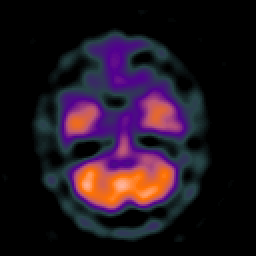

Huntington's Chorea, MR -- Slice #4

[Home][Help][Clinical] Slice 4